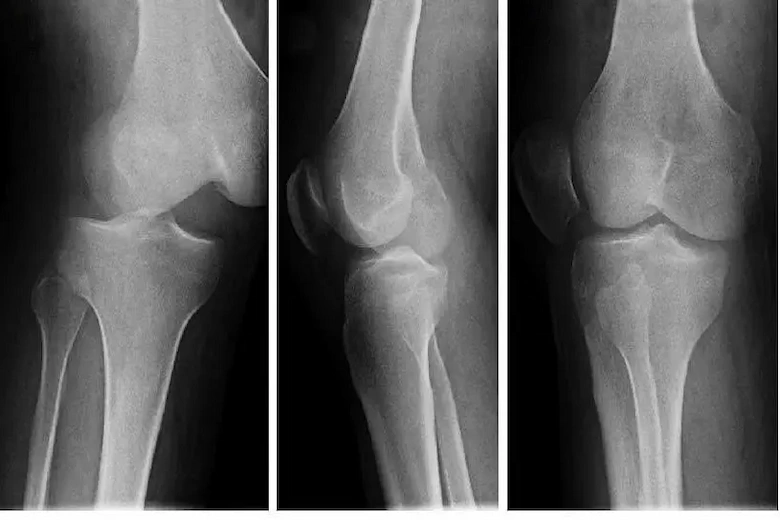

در بسیاری از موارد دررفتگی کشکک، فرد ممکن است تغییر شکل قابل مشاهدهای در جلوی زانو احساس کند. کشکک ممکن است به یک طرف متمایل شود یا حتی به وضوح بیرون زده باشد. این جابجایی نشان دهنده خارج شدن استخوان از شیار طبیعی خود در استخوان ران است و با درد شدید همراه خواهد بود. تشخیص تغییر شکل زانو توسط پزشک، همراه با معاینه بالینی و در صورت نیاز تصویر برداری، برای تعیین شدت آسیب و انتخاب روش مناسب برای درمان دررفتگی کشکک زانو، ضروری میباشد.